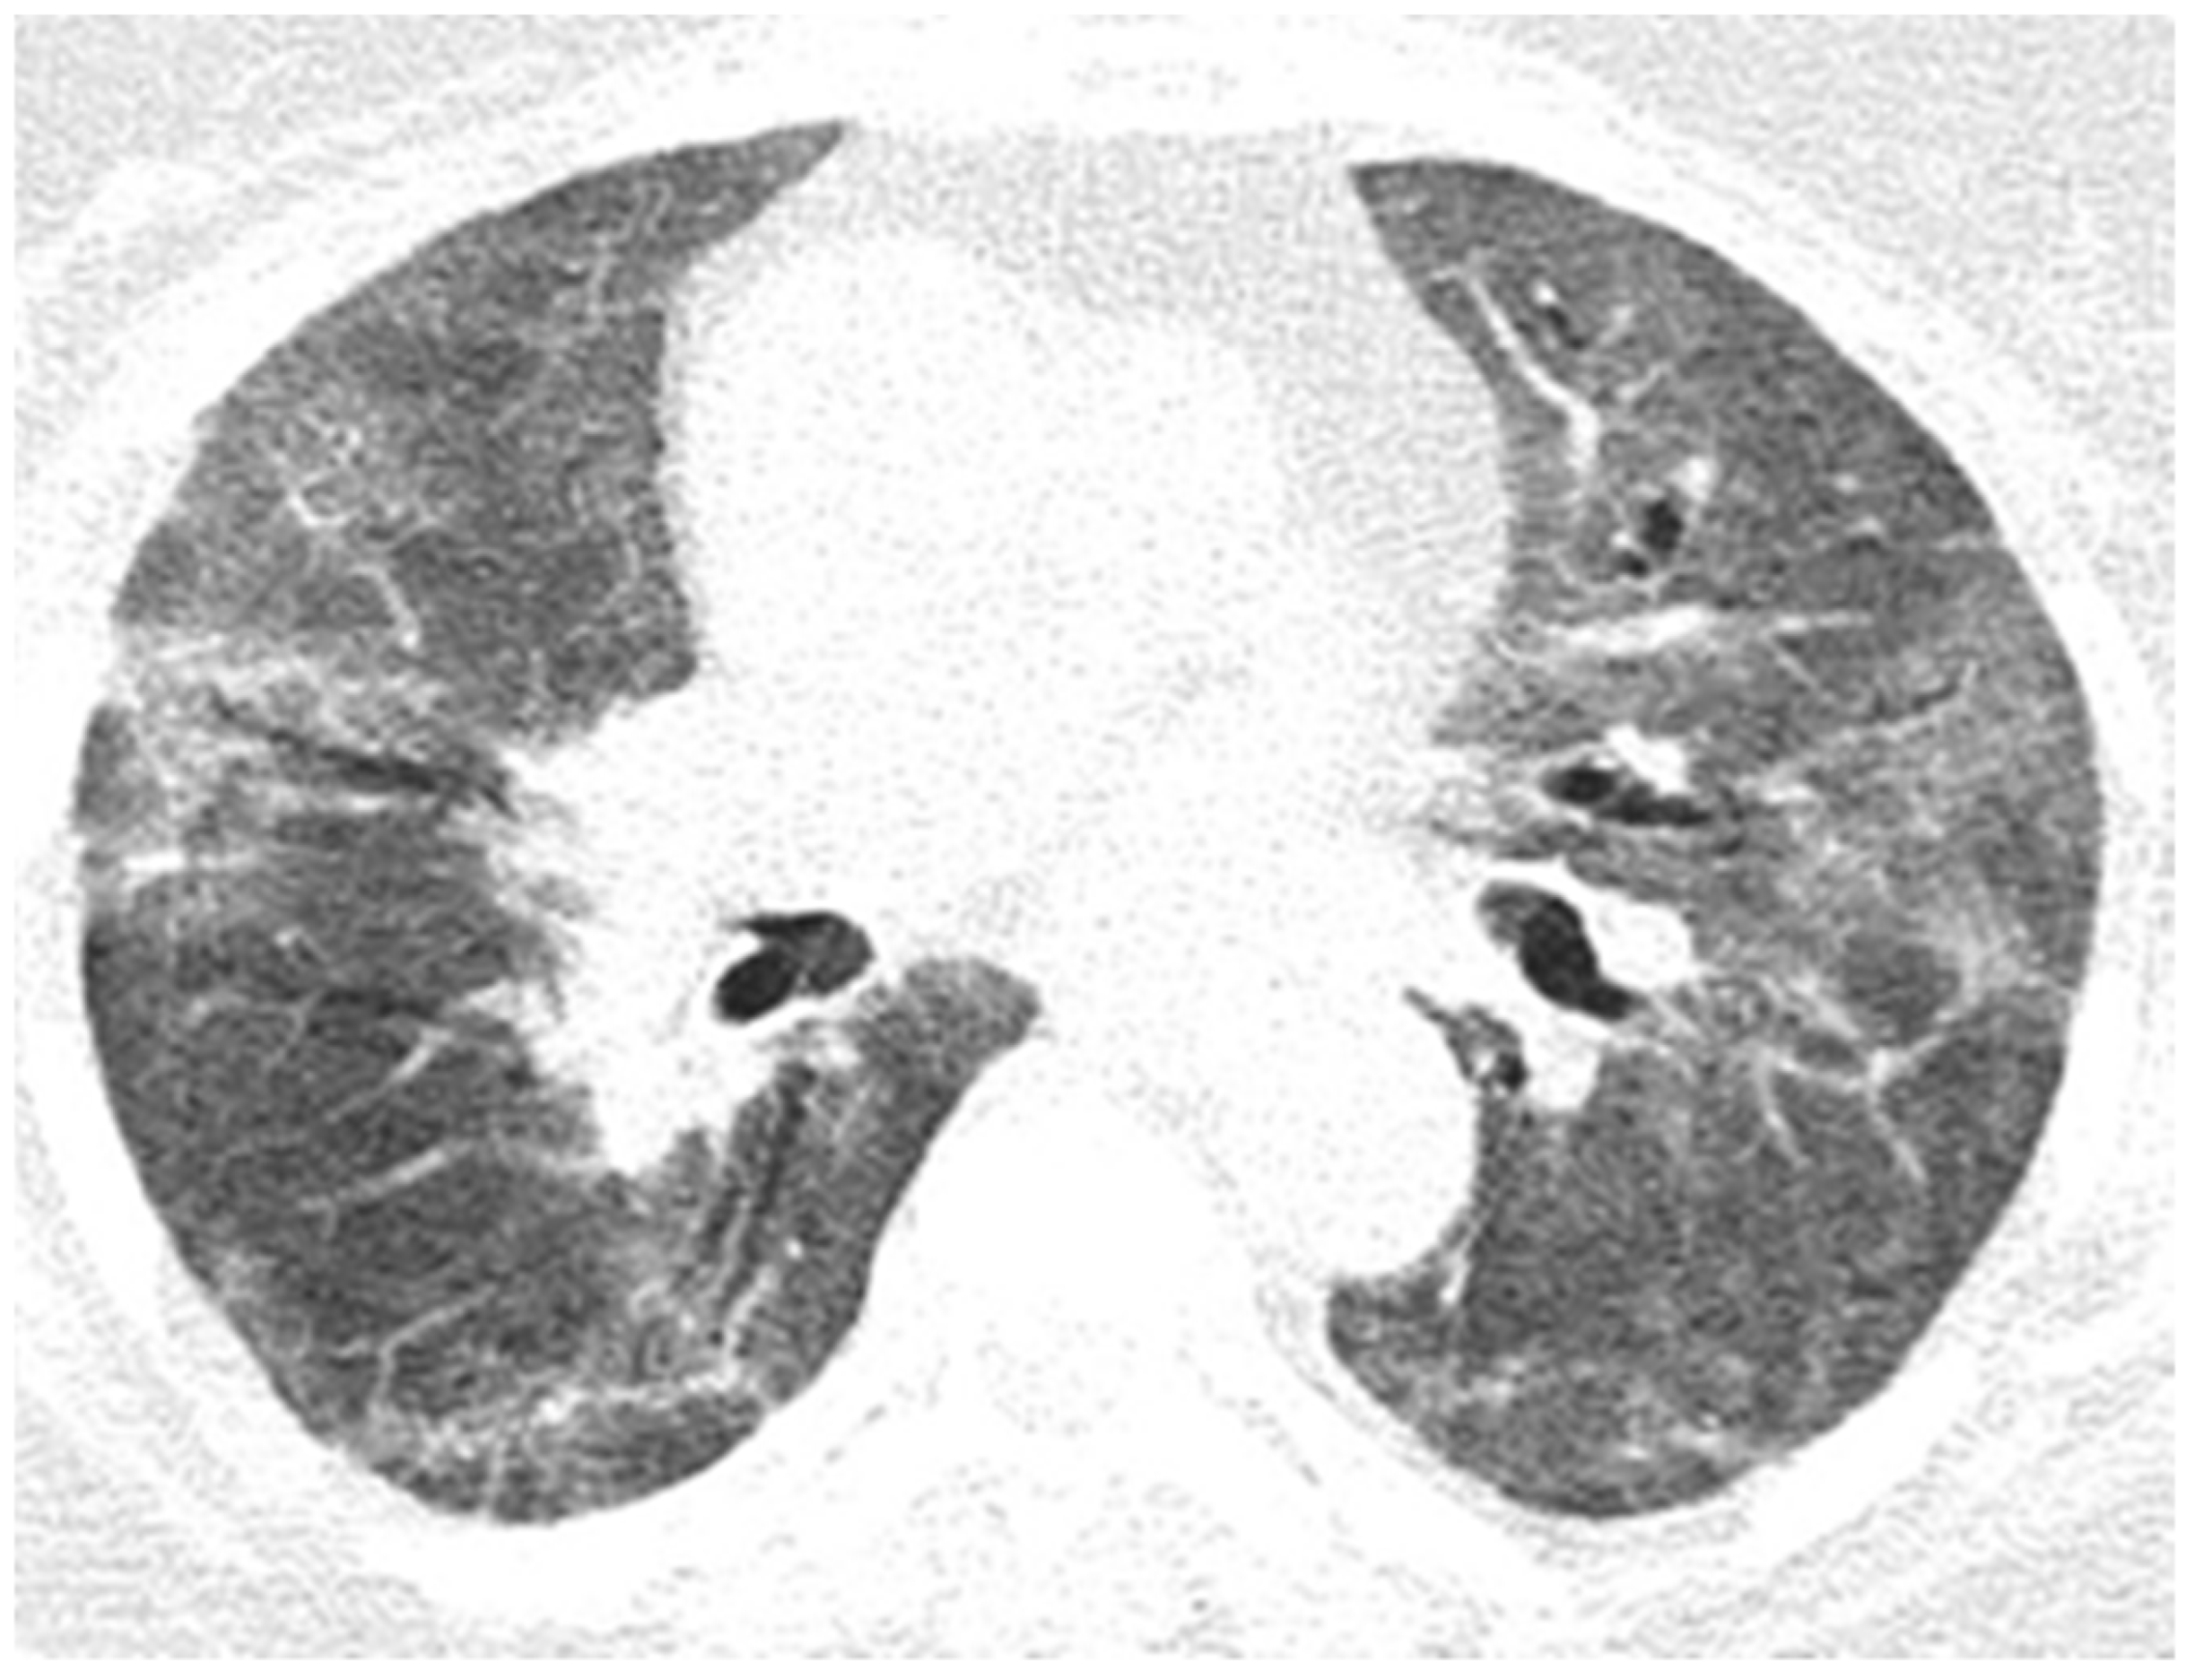

A chest CT showed alveolo-interstitial infiltrates with a tendency to confluence in bilateral lungs, compatible with COVID-19 pneumonia image-wise, CO-RADS 6-score severity (4/25p), slight pulmonary micronodules with sequelae appearance, and vesicular lithiasis. Seven days later, the repetition of chest CT showed pleurisy in the small right pleura, bilateral dorso-basal pulmonary condensation processes compatible with atelectatic processes, alveolo-interstitial infiltrates with a tendency to consolidation compatible with COVID-19 pneumonia, CO-RADS 6 image-frameable dimensional progression from a previous CT scan, a moderate severity score (11/25p), bilateral pulmonary micronodules with sequelae, and gallbladder lithiasis. An RT-PCR test was conducted, and the result was positive. A biological assessment revealed mild corrected hypokalemia, UTI with treated proteus mirabilis, hyperglycemia, and cardiac enzymes slightly altered.

Figure 10. Pulmonary CT images of the Case 10 patient show lesions with a polymorphic aspect, some under the form of inaccurately delimited areas of matt-glass clouding (a,b), and others with increased densities and associated interlobular septal thickness (a), randomly disposed at the level of both pulmonary fields. The tendency was to condensate some lesions from the level of the right anterior basal segment (a). Linear fibrosis outlines with retractile effect on the parietal pleura and on some subsegmental bronchial outlines, which could be highlighted especially at the inferior lingual level and at the level of the basal pyramid, bilaterally (a,b). In conclusion, fiber–alveolar–interstitial modifications are compatible with lesions of SARS-CoV-2 type in various phases of evolution, with a severity score of 13 (8 right lung, 5 left lung), determinable in moderate impairment.